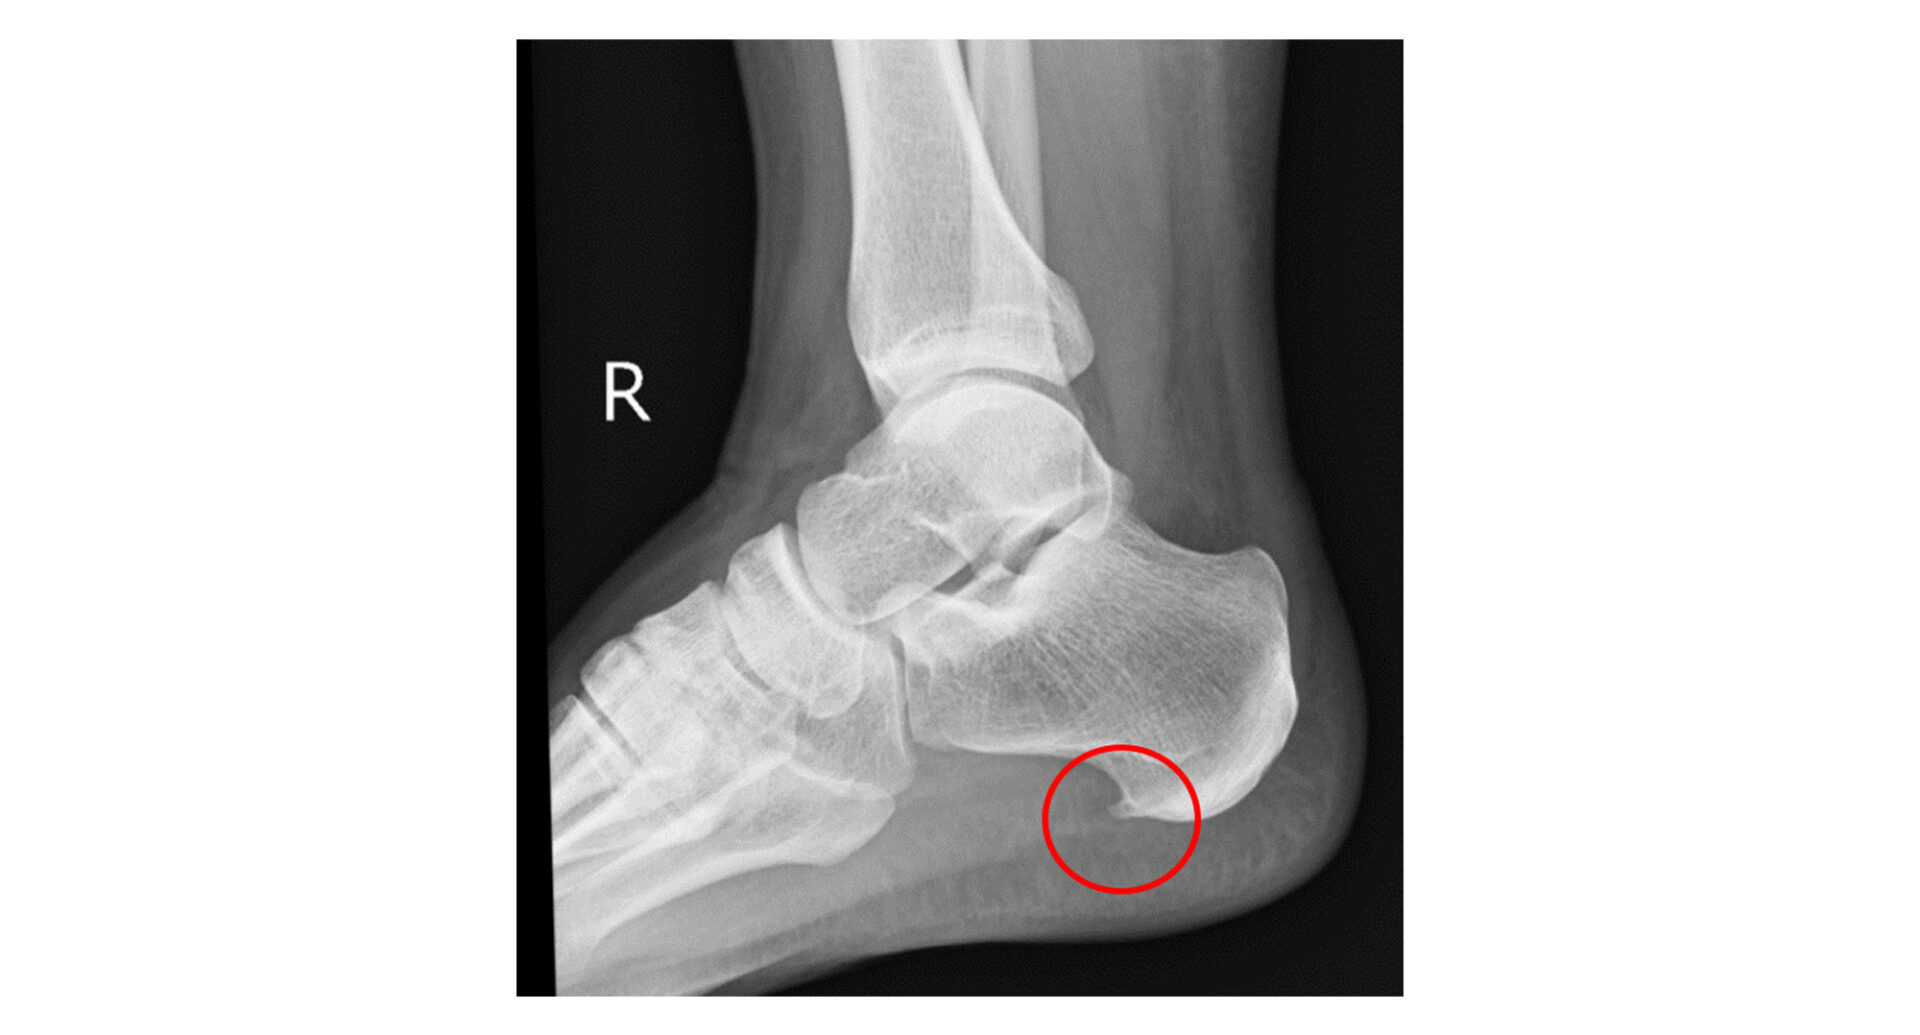

レントゲン(X線)検査

踵骨棘(かかとの骨に生じるトゲ状の突起)の有無は確認できます。

ただし踵骨棘は足底筋膜炎の直接原因ではなく、症状との相関も限定的とされているため、レントゲン単独での診断には限界があります。